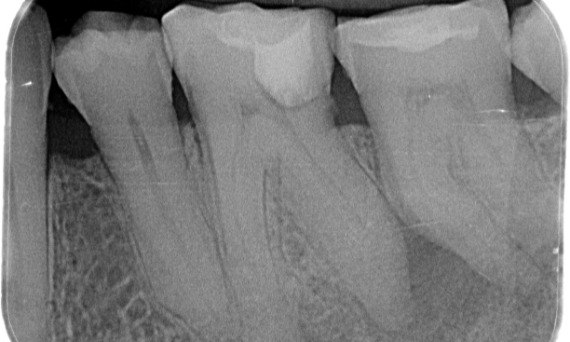

Vorher: Periapikale Radioluzenz primär an der distalen Wurzel und Verlust der Lamina dura an der mesialen Wurzel.

Nachher: In diesem Fall wurde TruNatomy gewählt, um einen kariesfreien Ansatz zu ermöglichen und sich auf den Erhalt des perizervikalen Dentins zu konzentrieren, insbesondere auf der mesialen Seite, wo der Zahn eine minimalere Restauration aufwies.

Bath, Vereinigtes Königreich